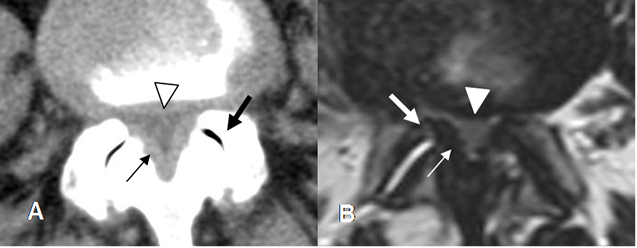

Fig 64. Canal estrecho lateral.

A: TAC axial en ventana de tejido y B: TAC axial en ventana de hueso. Estenosis del receso lateral, por hipertrofia de articulaciones intervertebrales y presencia de osteofito. (Flecha gruesa). Disminución de la grasa que rodea la raíz nerviosa. (Flecha delgada).